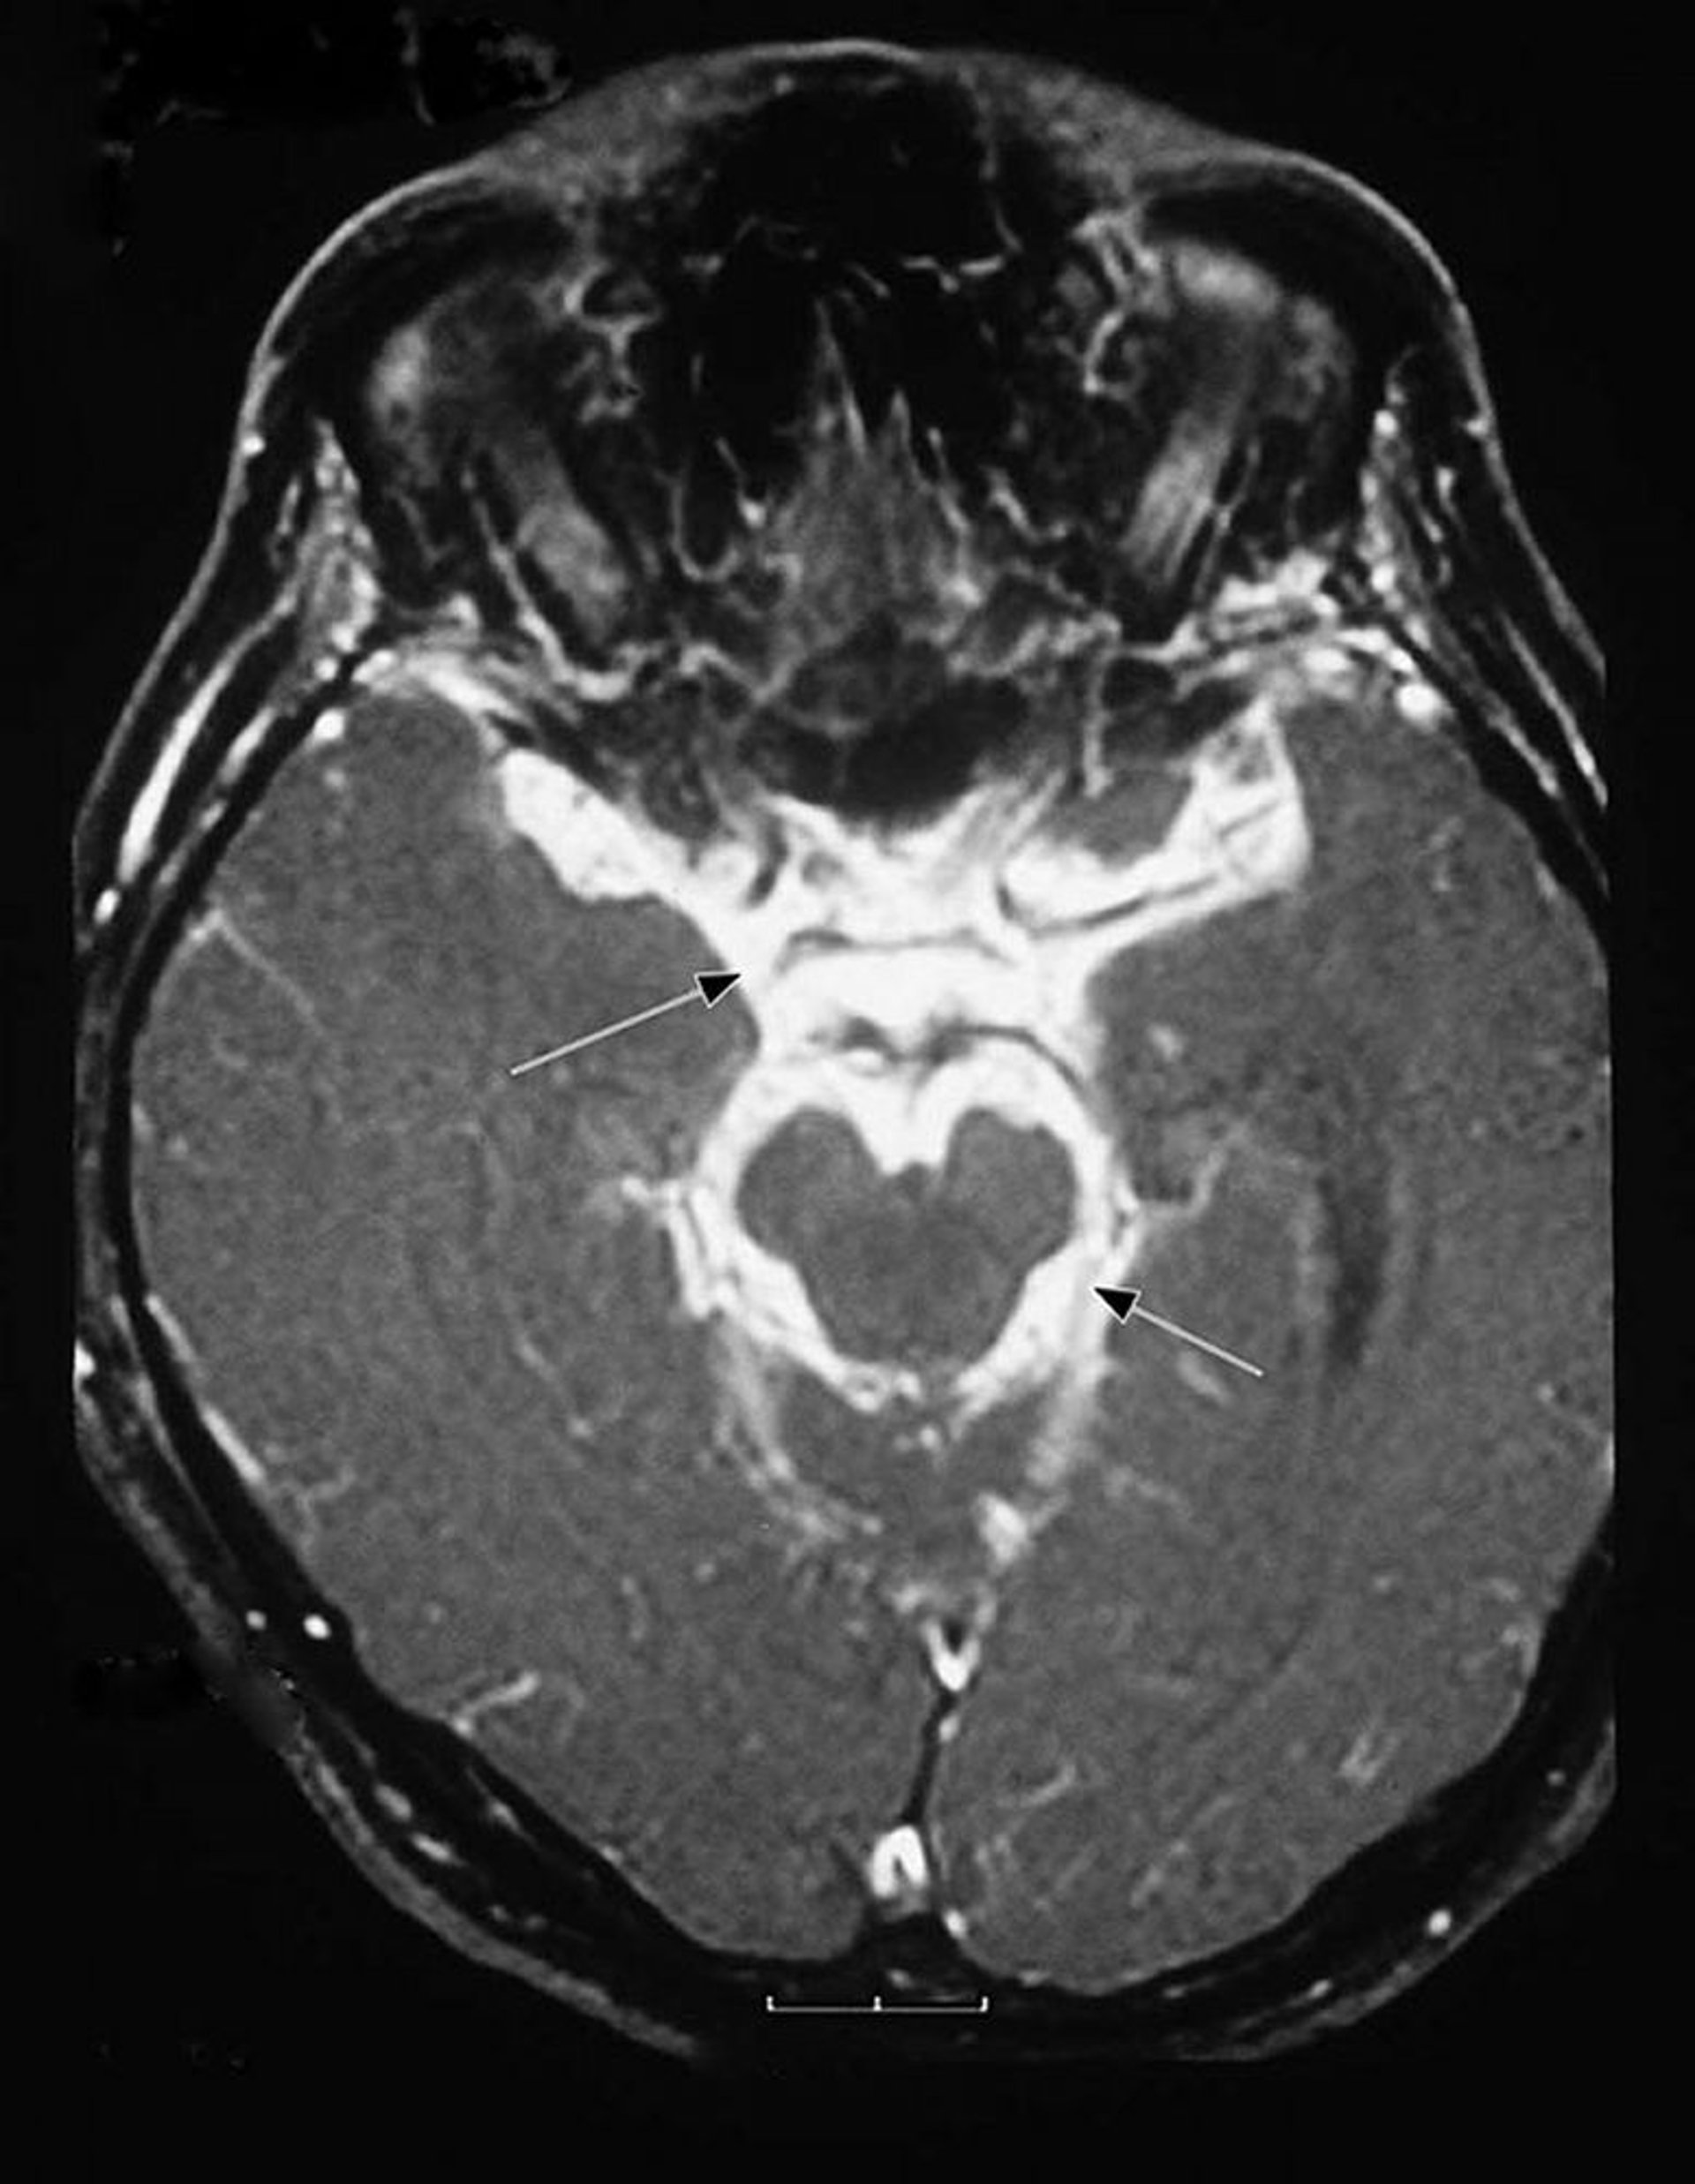

Meningitis tuberculosa

Esta resonancia magnética (RM) de un paciente con meningitis tuberculosa muestra un exudado inflamatorio intenso en la base del encéfalo (meninges basilares [flechas]) y alrededor del tronco encefálico.

Image courtesy of John E. Greenlee, MD.